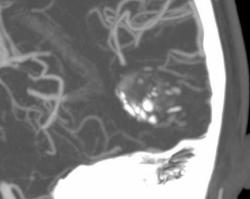

Еще одна сосудистая мальформация - кавернозная ангиома или кавернома. Раньше относили к опухолям.

Видна группа сосудистых лакун неправильной формы, кальцинаты. Перифокальных изменений нет.

Больному также проводили МРТ (снимков у меня нет), которая очень хорошо выявляет каверномы.